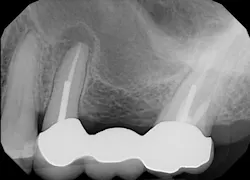

The patient, a 63-year-old female, presented for an emergency visit. She explained her situation, complaining of pain and a lump on the top-left quadrant of her mouth. After an oral evaluation and x-ray (figure 1), it was discovered that she had a large draining granuloma with swelling in the mucobuccal fold near teeth Nos. 12–14 due to a chronic periapical abscess (figure 2).

After using a round burnisher and blow test to determine that there was no perforation to the sinus and the membrane was still intact, the laser was used at a spot size of 1.25 mm, on low power mode, and without mist or air to debride the medial superior area of the bony defect. X-rays were taken following immediate placement of bone-graft material to display the site after using Solea to remove bone and granulation tissue (figures 6 and 7). The entire procedure, including the bone graft, took approximately 40 minutes from start to finish.